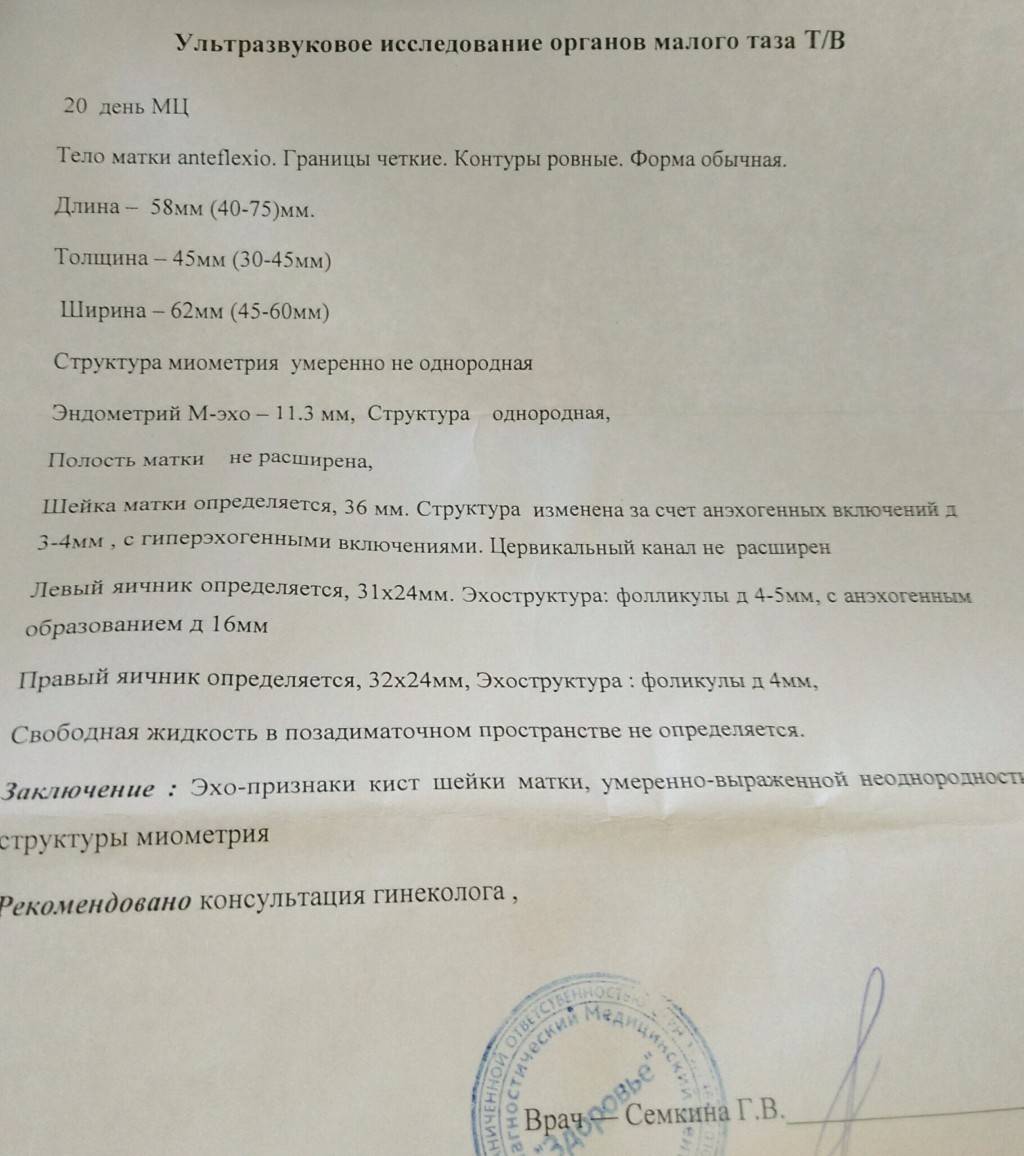

УЗИ малого таза

Почему разные заключения на УЗИ?